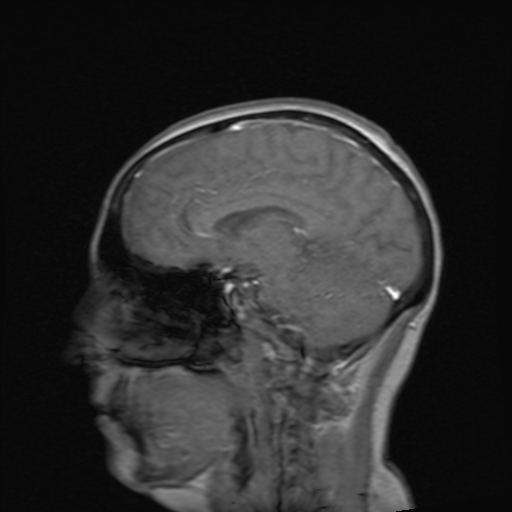

Picture the person ahead of you in a car stopping suddenly and you reacting by hitting the brakes without thinking. This is the immediate processing of your senses through the Thalamus sending signals to the Amygdala to react. It is fight or flight. Your heart beats fast and breathing may accelerate. Adrenaline is sent quickly throughout your body. Very shortly after the initial fight or flight response the Prefrontal Cortex gets the information and we can have a more logical response. It is at this point that we can normally begin to calm. Additional hormones are sent to our body to help us calm down. This is normal.

For many people with trauma, reactions do not work that way. Some people remain in the heightened state. The Prefrontal Cortex remains offline keeping the person in a constant state of panic. This panic can be elevated such as the continued fight and flight, or it can become a freeze state. In other cases it can become a complete shut down of sensory and related functions.

When I walk into Walmart I become quiet, overstimulated. I begin to shut down. This does not compare to the shut down that occurs when I experience a flashback or have to discuss trauma that has happened in my life. During shut down the senses no longer work properly. My vision becomes blurred; I don’t hear music or background noise; my body goes numb, limp, or stiff; and other areas shut down. The hardest part for me is that my mind experiences the flashbacks, but my ability to speak shuts down. Broca’s area (the speech center of the brain) actually shuts down when experiencing or re-experiencing trauma. When I stop talking and/or appear disconnected it is probably because what is being discussed is too difficult for me to focus on. Be patient with me. I am trying, but I am not ready to experience what some people think I am ready to experience.